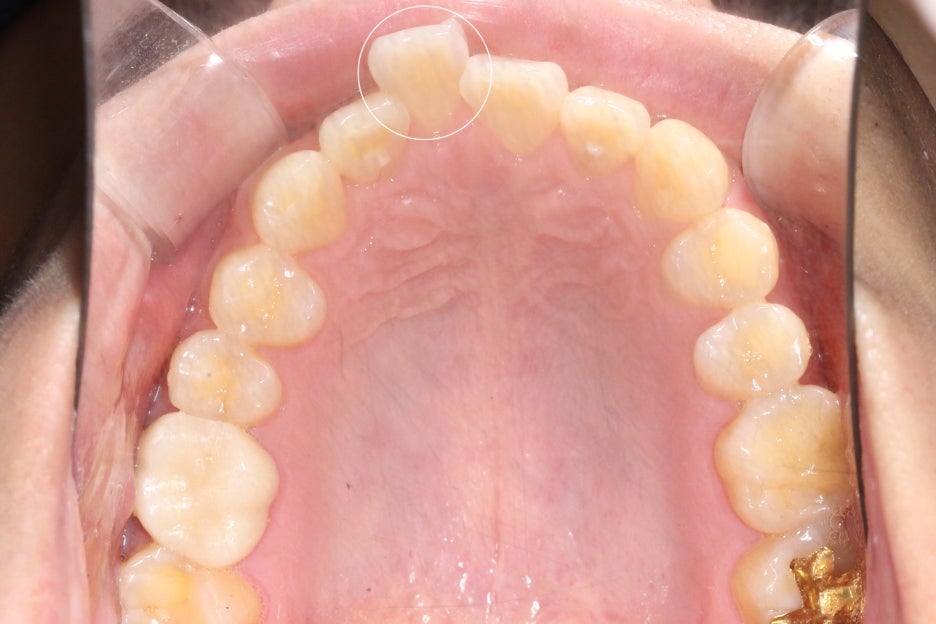

논현동치과 윗니부분교정 후 치아의 배열을 보면

바깥으로 누워있듯이 뻐드러져 있던

11번 치아가 자연스럽게

교정된 것을 확인할 수 있으며

전체적인 안모의 모양도 곡선을 그리며

U-모양으로 형성되어 있어 심미적인 모습인데요,

치아가 배열된 모습이 U-모양에 가까울수록

이상적인 안모가 될 수 있습니다.